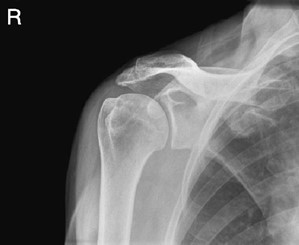

Świadczenie usług medycznych …

Na radiogramie uwidoczniono

Ilustracja do pytania 8

A. zwichnięcie stawu ramiennego w projekcji przednio-tylnej.

B. prawidłowy obraz stawu ramiennego w projekcji barkowo-pachowej.

C. prawidłowy obraz stawu ramiennego w projekcji przednio-tylnej.

D. zwichnięcie stawu ramiennego w projekcji barkowo-pachowej.